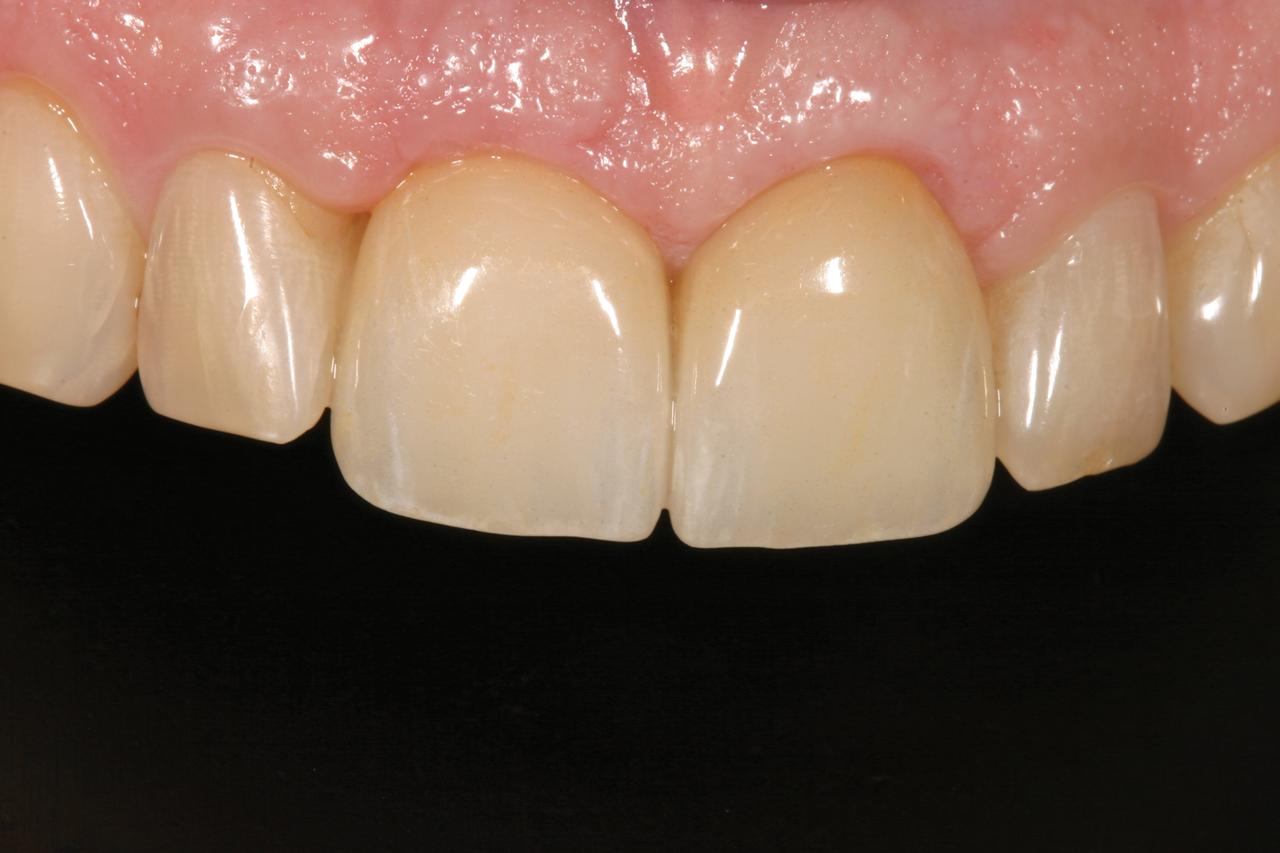

Fig 5. Successful final clinical result of the implant restoration and adjacent teeth.

Figure 5